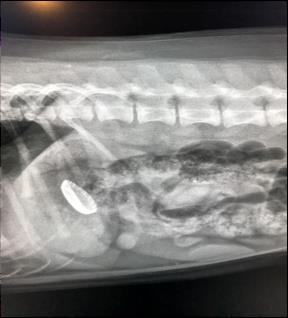

Voorbeeld 5. Gastroscopie: Saté-stokje verwijderd

Voorbeeld 6. Gastroscopie: ijscrème bakje verwijderd

Voorbeeld 7. Gastroscopie: Kroonkurk verwijderd

Zowel de maag als de slokdarm kunnen vlot met endoscopie in beeld gebracht worden (ook bij kleinere honden). Dit kan noodzakelijk zijn bij het vermoeden van maagontstekingen, maagzweren of tumorale processen maar ook bij opname van vreemde voorwerpen. Deze voorwerpen kunnen dan via endoscopische begeleiding verwijderd worden zodat een ingrijpende chirurgie niet nodig is.